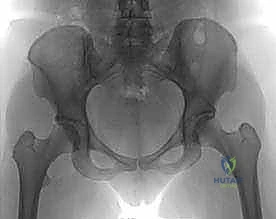

عندما تكون هذه الزاوية أكبر من الطبيعي (Coxa Valga) أو أصغر من الطبيعي (Coxa Vara)، يحدث خلل شديد في توزيع وزن الجسم على مفصل الورك. هذا الخلل يؤدي إلى تركيز الضغط على مساحة صغيرة جداً من الغضروف المفصلي، مما يسرع من تآكله ويؤدي إلى خشونة مبكرة (Osteoarthritis).

هنا يأتي دور الجراحة التقويمية التي يجريها الأستاذ الدكتور محمد هطيف؛ حيث يتم إجراء قطع عظمي دقيق في المنطقة الواقعة بين المدور الأكبر والمدور الأصغر (Intertrochanteric Region)، وهي منطقة تتميز بتروية دموية ممتازة مما يضمن التئاماً سريعاً للعظم. بعد القطع، يتم تعديل الزاوية لتوزيع الأحمال بشكل متساوٍ على مساحة أكبر من الغضروف السليم، مما يوقف أو يبطئ بشكل كبير عملية التآكل.

- التصوير الشعاعي المتقدم: استخدام الأشعة السينية بوضعيات محددة، والأشعة المقطعية (CT Scan) ثلاثية الأبعاد، والرنين المغناطيسي (MRI) لتقييم حالة الغضروف بدقة.